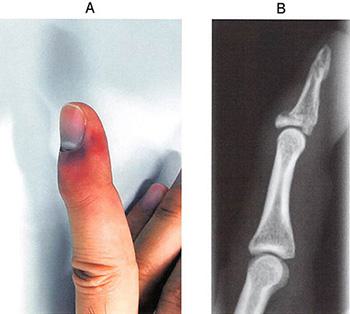

36歳の男性。手にバスケットボールが当たって受傷した。来院時の手指の写真(A)とエックス線単純写真(B)とを示す。この病態として正しいのはどれか。